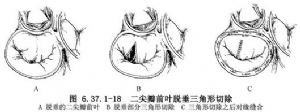

①瓣膜裂隙:前瓣裂隙修复与部分房室隔缺损的二尖瓣裂隙修复相同,应用4-0无创伤线间断缝合裂隙。在成人瓣膜裂隙大,并有组织缺少时,可用经戍二醛处理的自体心包片修补裂隙。为了增加瓣膜活动度,尚需切除裂隙的异常腱索和邻近增厚的瓣叶组织。三叶二尖瓣产生关闭不全时,矫治的目的是恢复三叶的形状和功能而不是正常瓣解剖。先向左心室内注生理盐水,观察瓣膜关闭不全的位置。通常需做前外和后外交界折叠(图4)。间隔交界关闭不全应闭合交界远端,同时缝合裂隙,防止晚期关闭不全。后瓣裂隙除缝合瓣叶外,相应部位的瓣环也应折叠。

前瓣腱索延长修复方法有腱索缩短术,将乳头肌尖端劈开一纵沟,用5-0缝线绕过腱索,穿过纵沟的两侧,拉紧缝线将腱索埋在沟内,然后缝合乳头肌切口(图6.37.1-16)。如乳头肌细小,则直接做“8”字缝合把腱索折叠固定在乳头肌上,再用垫片褥式缝合穿过腱索和乳头肌加固;人工腱索成形术,为近年来文献报道的新方法。用4-0的膨体聚四氟乙烯线从前瓣边缘心室面缝到心房面。然后缝线距乳头肌尖端3~4mm穿过乳头肌,加垫片并提起缝线,测量后瓣腱索长度,在与之相等的高度打结(图6.37.1-17)。此方法也适用于腱索发育不良和腱索断裂;三角形切除,在脱垂的瓣叶处做窄的等边三角形切除,通常不超过1.5cm。切缘两侧直达正常粗壮的腱索,能够支持重建的瓣叶。有些病例脱垂区域广泛,可做两处三角形切除(图6.37.1-18)。双孔二尖瓣成形,即用4-oprolene缝线将脱垂的瓣叶对缘缝合,使瓣成为双开口。